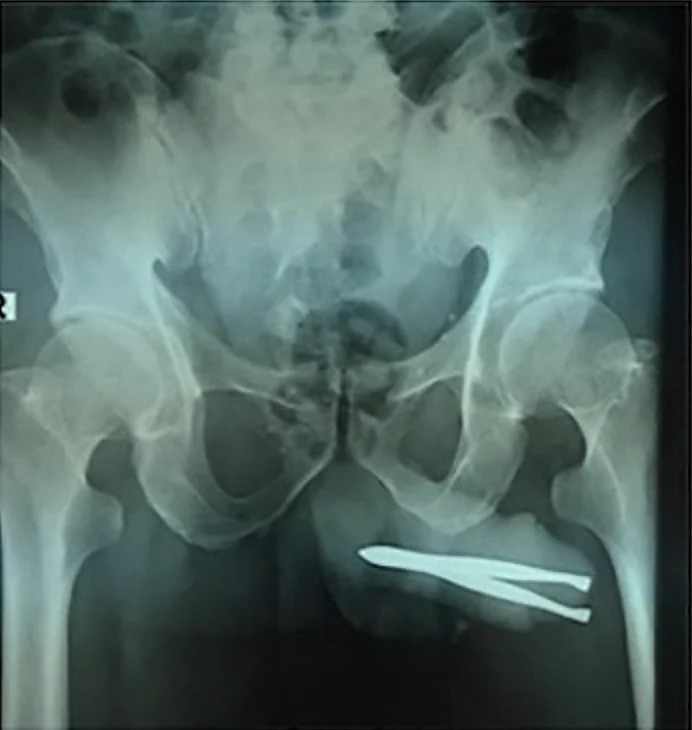

כאשר הרופאים גילו את העצם הזר שחדר לתוך קצה איבר מינו, הם הופתעו לגלות שהוא עדיין היה מסוגל להטיל שתן, אם כי בכאב ובקושי רב. צילומי הרנטגן חשפו את מלוא היקרף הבעיה, שכן הפינצטה הייתה תקועה בחוזקה בדרכי השתן שלו.

הרופאים נאלצו לבצע הליך חילוץ עדין בהרדמה. הם חתכו חתך קטן על איבר המין על מנת להרחיב את פתח השופכה ולהסיר את הפינצטה בבטחה. לאחר מכן הם סגרו את הפצע עם שלושה תפרים. למרבה המזל לא היו סיבוכים כמו דיום או זיהום.